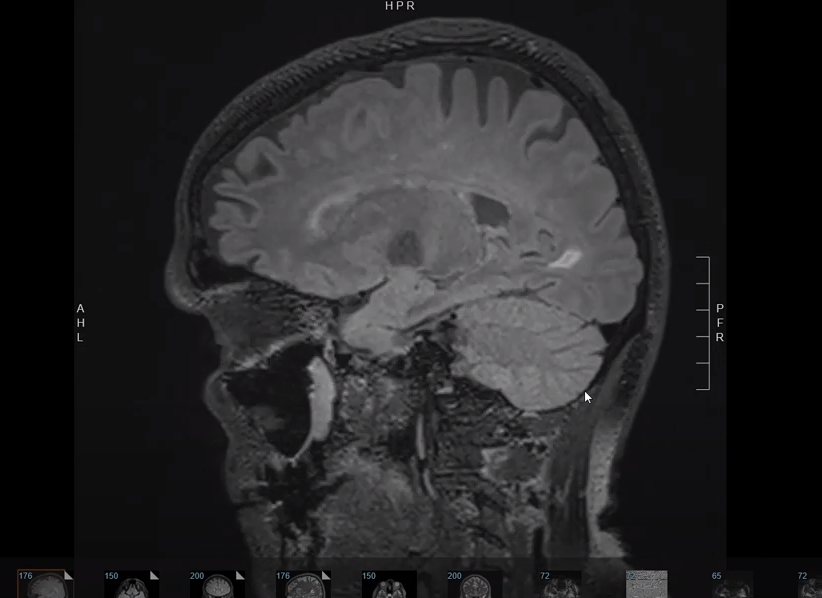

MRI of Severe Headache

Dr. Elahi describes Brain MRI images of 60+ yo with intermittent headaches showing signs of small vessel ischemic changes. Images demonstrate common findings of MRI’s done of patients presenting with migraine headaches and/or risk factors for cerebrovascular disease including elevated cholesterol, high blood pressure, and strong family history of vascular risk factors.